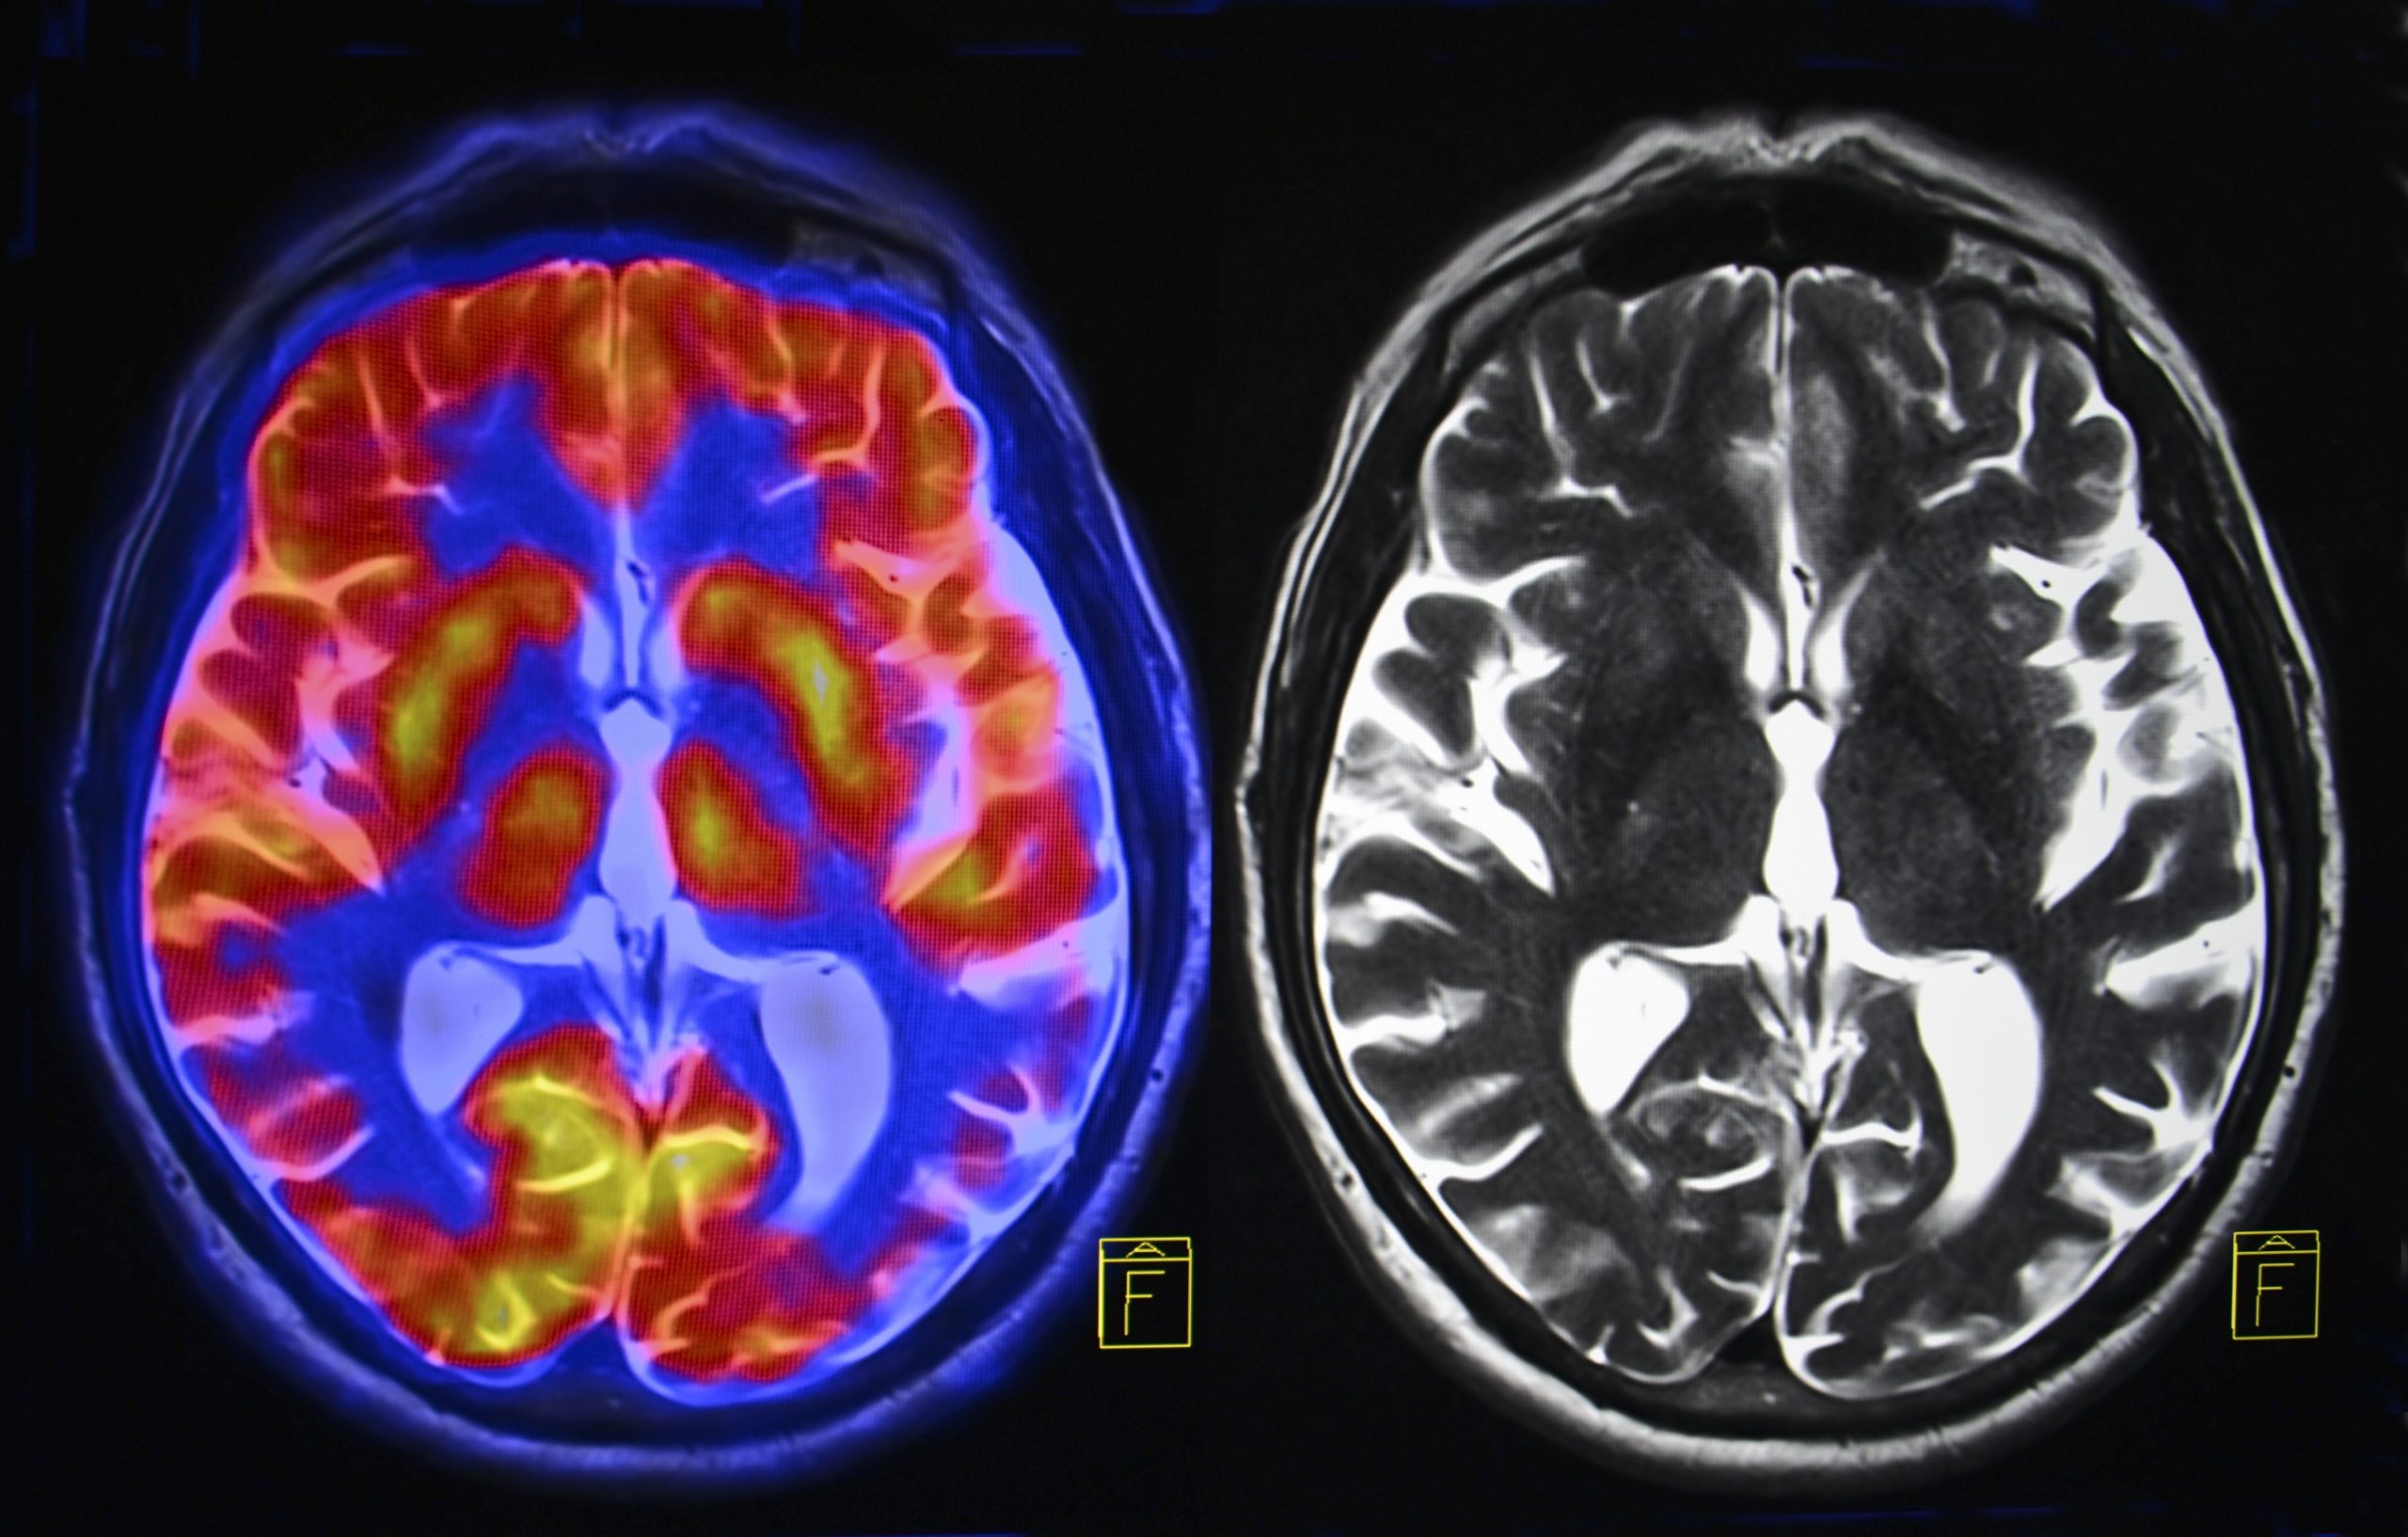

Демиелинизирующие заболевания мозга: МРТ изображения